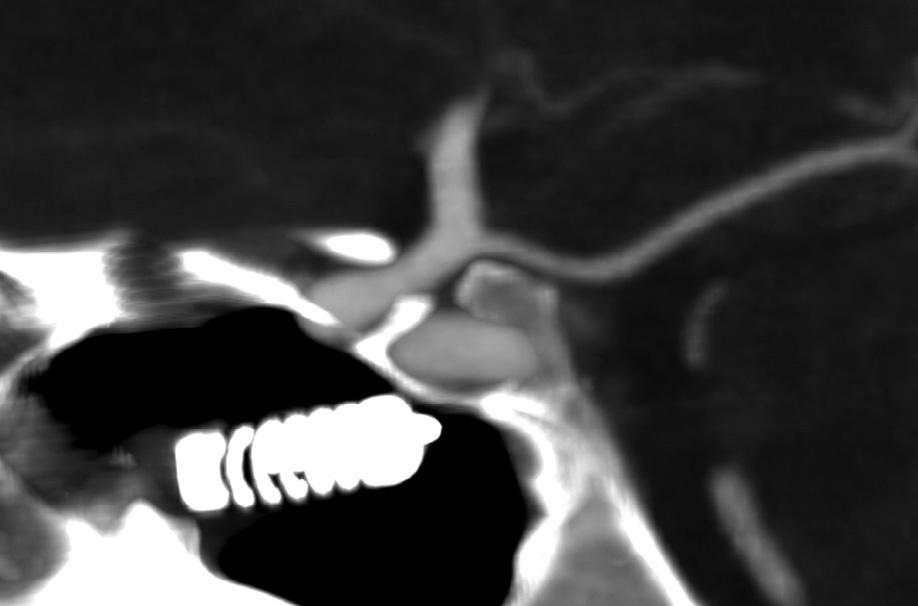

AllheadCTinterpretationshouldfollowaconsistent searchpattern,toinsurethatincidentalfindingsarenot overlooked.Thesymmetryoftheventricles,sulci,andcisternsshouldbeassessed;midlineshift,sulcaleffacement, herniation,masslesions,andbleedsintheepidural,subdural,subarachnoid,andparenchymalcompartmentsof thesupratentorialandinfratentorialspacesshouldbe excluded.Extracranially,theglobes,orbits,paranasal

Fig.1.9. Coronalandsagittalreformattedimagescanmitigate volumeaveragingandstreakartifactsfromadjacentbony structures,improvingtheconspicuityofsubtlehemorrhage comparedtothatofthick-sliceaxialimagesalone.